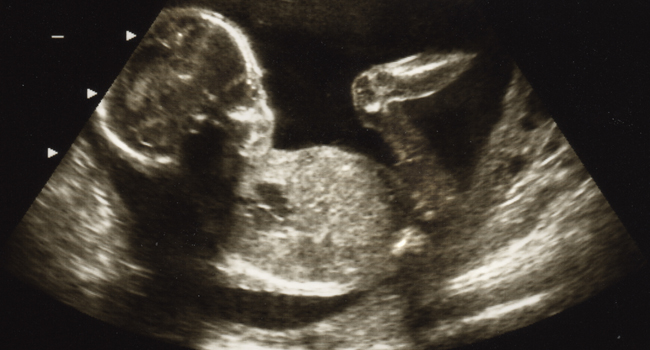

Pemeriksaan standar untuk USG adalah 2D. Tapi, beberapa tahun ini tren USG dalam bentuk 3D dan 4D lebih digemari. Menurut US National Library of Medicine National Institute of Health, ketiganya memiliki tujuan yang sama, yaitu melihat pertumbuhan janin. Agar Anda lebih mudah memilih, berikut perbedaannya.

1. USG 2D

Hasil USG berupa foto hitam putih, dan hanya terlihat dari satu sisi, sehingga masih terlihat samar namun tetap dapat digunakan untuk melihat organ internal bayi. Jika dokter mencurigai ada kelainan, biasanya Anda akan disarankan melalukan USG berdimensi lebih tinggi. USG 2D dilakukan setiap trimester.